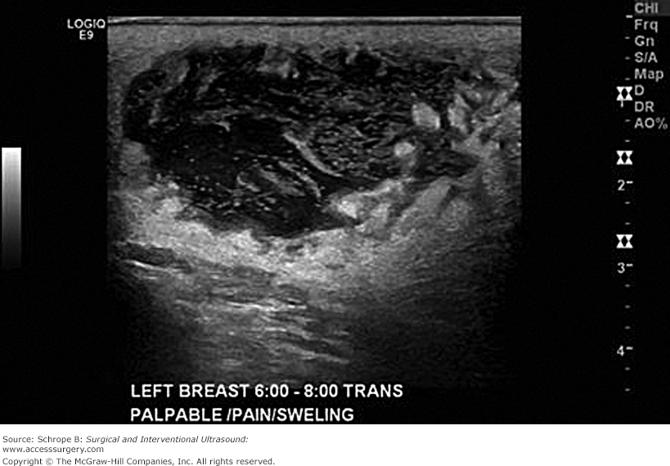

Staphylococcus aureus and Streptococcus species are the organisms most frequently recovered from nipple discharge from an infected breast. Breast abscesses are typically seen in staphylococcal infections and present with point tenderness, erythema, and hyperthermia. These abscesses are usually related to lactation and occur within the first few weeks of breast-feeding. Staphylococcal infection can result in subcutaneous, subareolar, interlobular (periductal), and retromammary abscesses (unicentric or multicentric), necessitating operative drainage of fluctuant areas. Preoperative ultrasonography is effective in delineating the extent of the drainage procedure, which is best accomplished via circumareolar incisions or incisions paralleling Langer's lines. While staphylococcal infections tend to be more localized and may be located deep in the breast tissues, streptococcal infections usually present with diffuse superficial involvement. They are treated with local wound care, including warm compresses, and the administration of intravenous antibiotics (penicillins or cephalosporins). Breast infections may be chronic, possibly with recurrent abscess formation. In this situation, cultures may reveal acid-fast bacilli, anaerobic and aerobic bacteria, and fungi. Uncommon organisms may be encountered and long-term antibiotic therapy may be required.